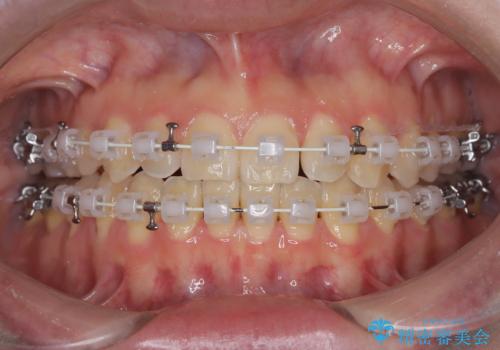

【ワイヤー矯正】一番後ろの奥歯でしか噛んでいないかみ合わせを治したい

最初は、一番後ろの奥歯でしか噛んでいない状態で、上下の前歯の先端がちょうど当たる切端咬合でした。

口腔習癖の改善及び、ワイヤー矯正にて歯列の平坦化を行うことで咬合を確立することができました。